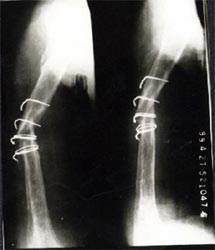

病例三、

肱骨骨不连的骨断端多有硬化而骨干骨质疏松、遗留有以往手术钢丝、

钉孔,骨吸收骨干变细皮质变薄,有严重骨缺损。

带锁髓内钉在骨组织和钉体之间提供较均匀的弹性应力分布,避免钢板内固定时

广泛的软组织剥离,抗旋转作用强于可屈髓内钉,不需外固定,对断端稳定性好